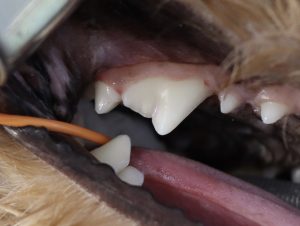

こちらの写真の症例は下顎の切歯(前歯)がぐらぐらしているという主訴で来院されました。

肉眼的にも歯肉が後退しているのが分かります。

最初の写真に比べると切歯の背が高くなったように見えますが、これは後退した歯槽骨に合わせて切開した歯肉を縫合しているためです。

切歯同士の隙間が開くことで新たな歯垢の付着を最小限に、かつ歯ブラシや歯間ブラシで磨きやすくしています。